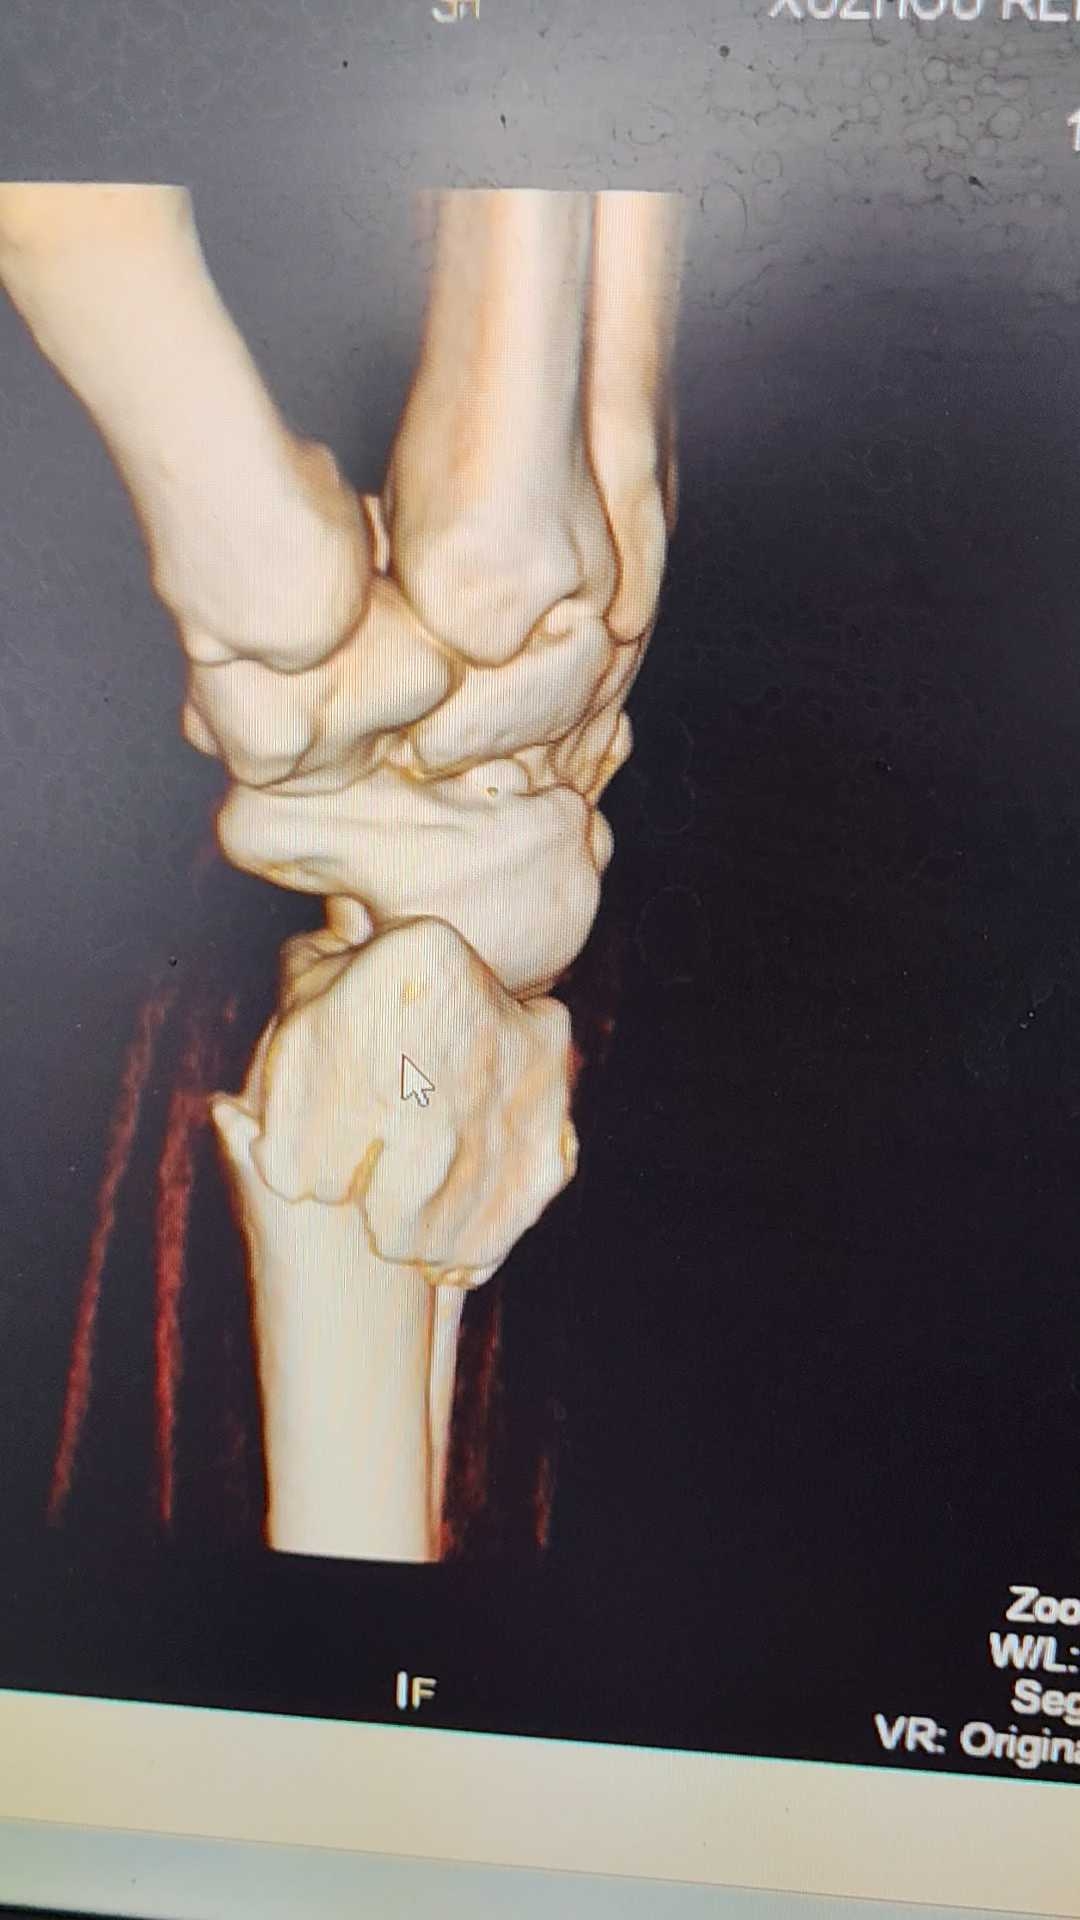

女,60岁,外伤桡骨远端骨折尺骨茎突骨折复位后效果